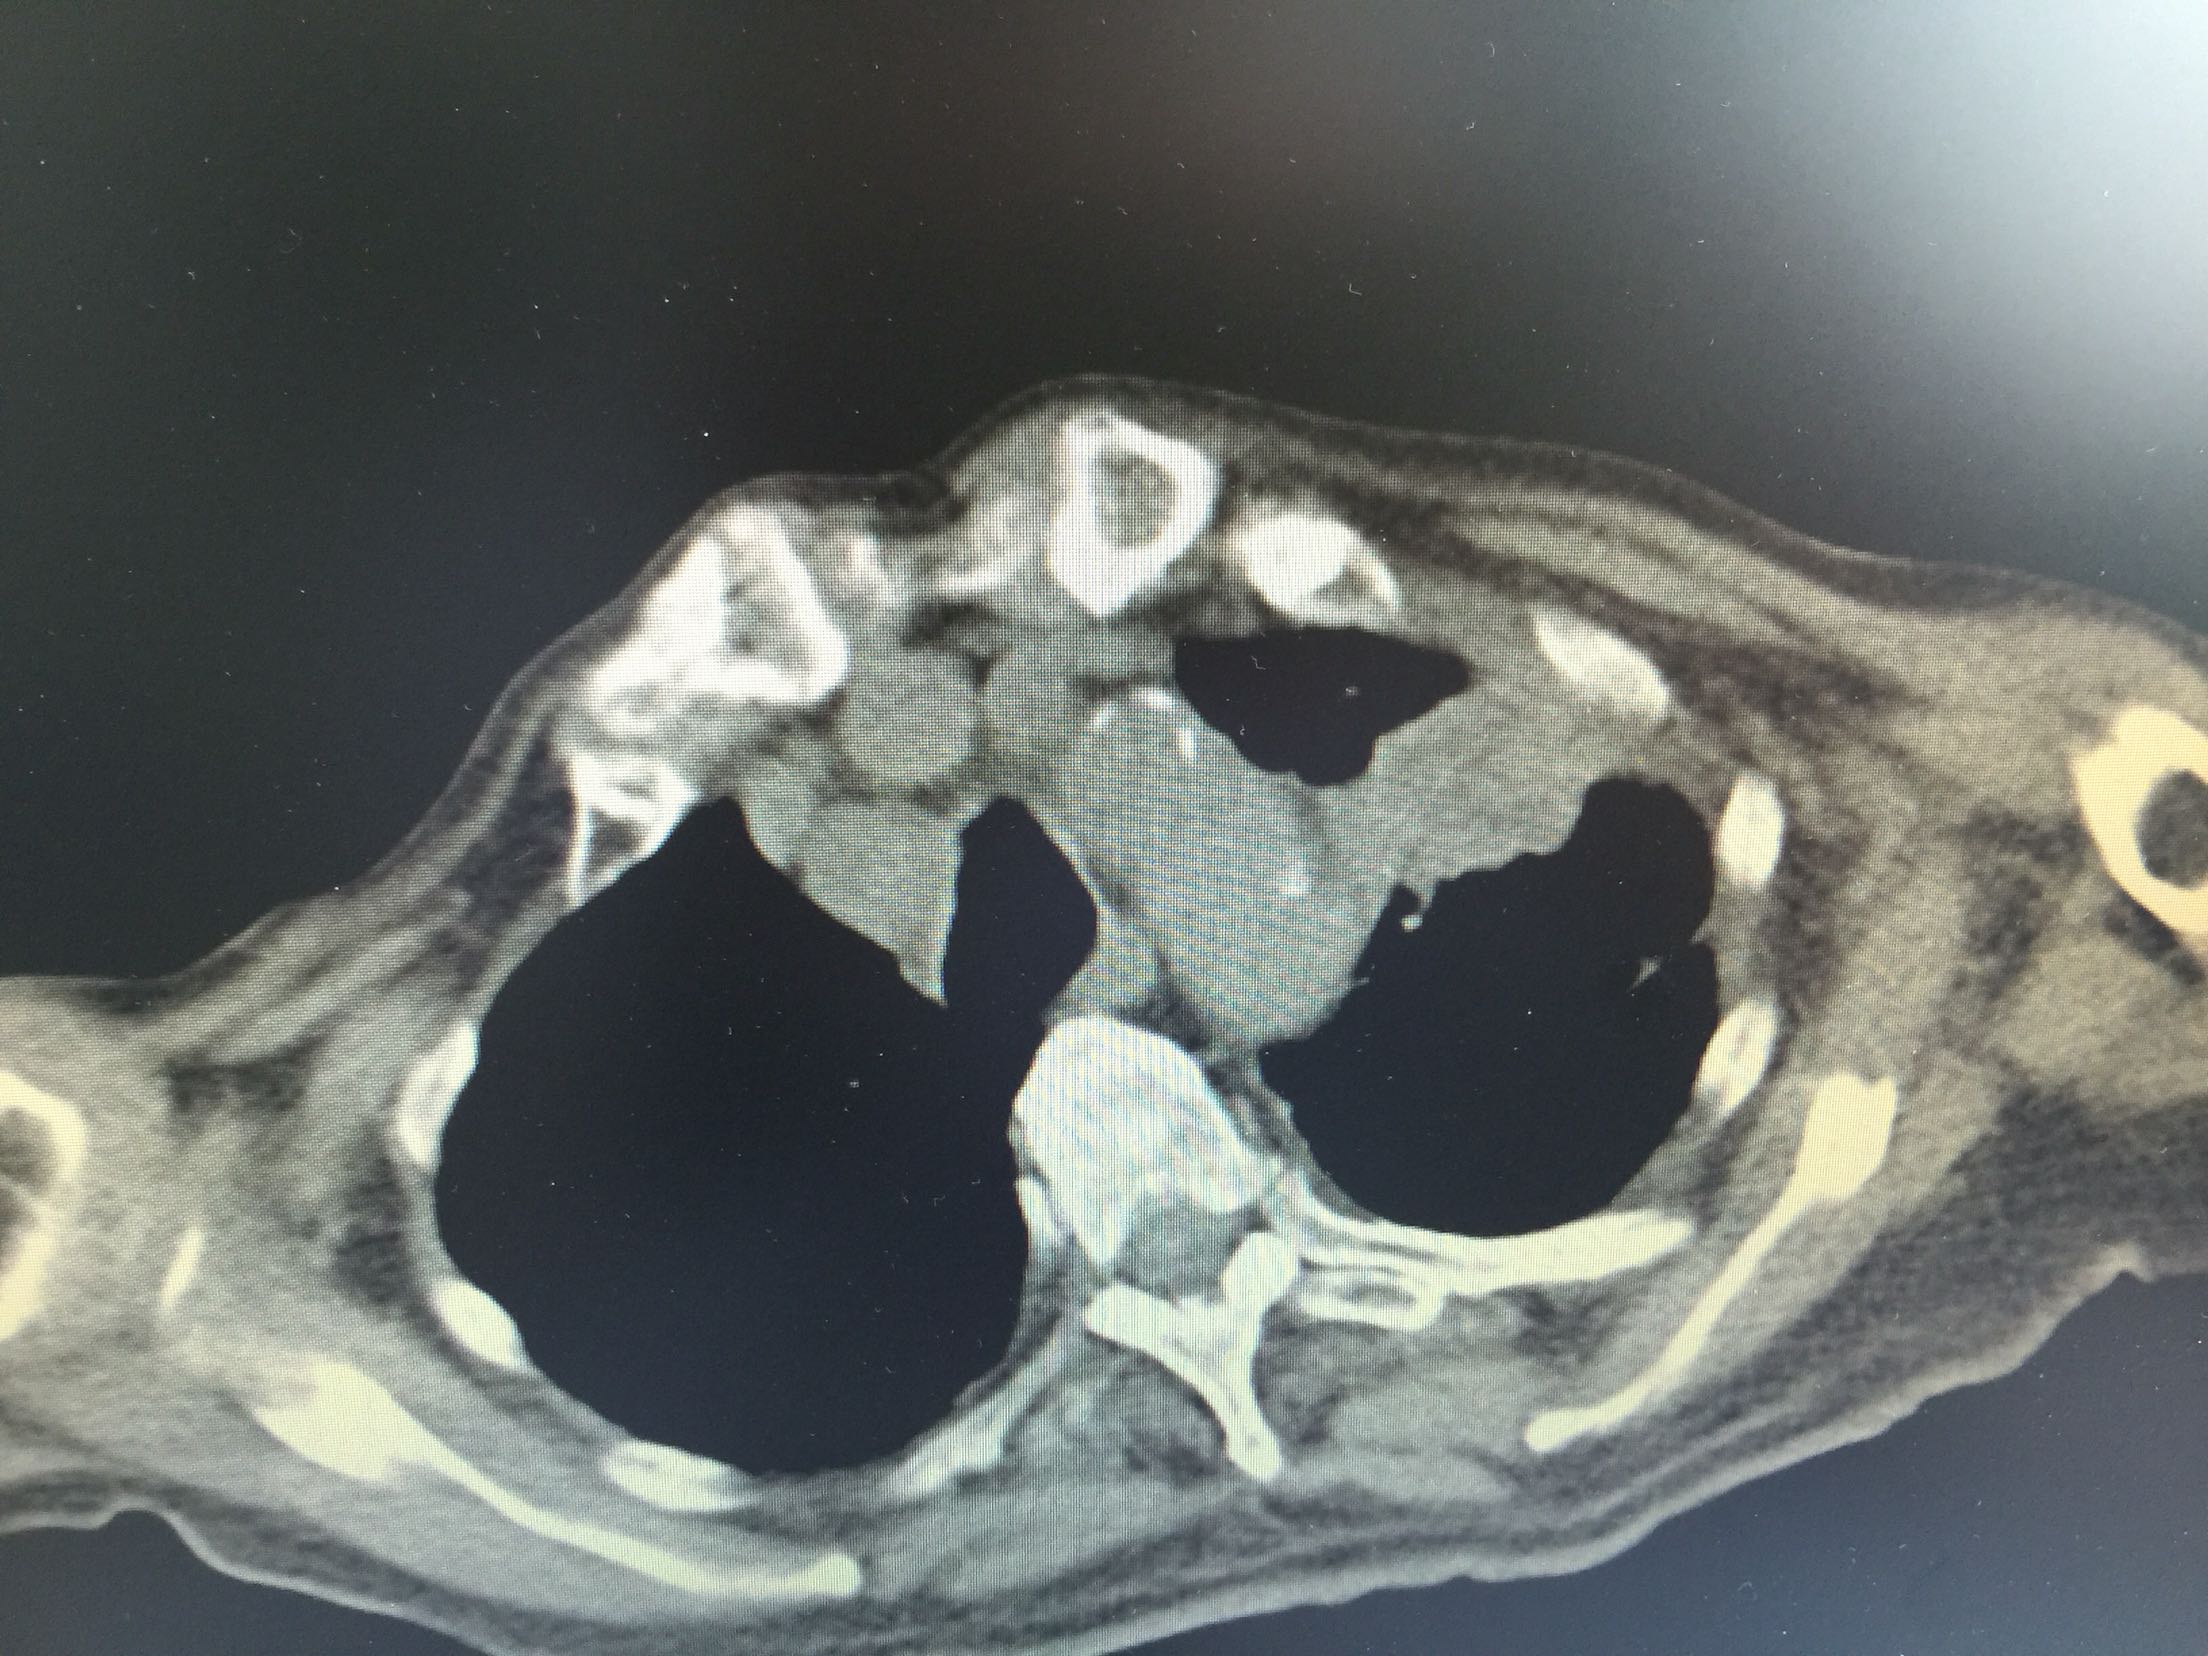

肺癌脑转移1例。

女,81岁,以“意识障碍1天”入院。

查体:浅昏迷,双眼向左侧凝视,双瞳孔等大正圆,直径3.0mm,对光反射灵敏,四肢不自主运动,肌张力正常,腱反射卄,Babinski征R-L-,脑膜刺激征阴性。

1.肺癌脑转移。 治疗:营养神经、脱水、抗感染、化痰、维持离子平衡治疗。